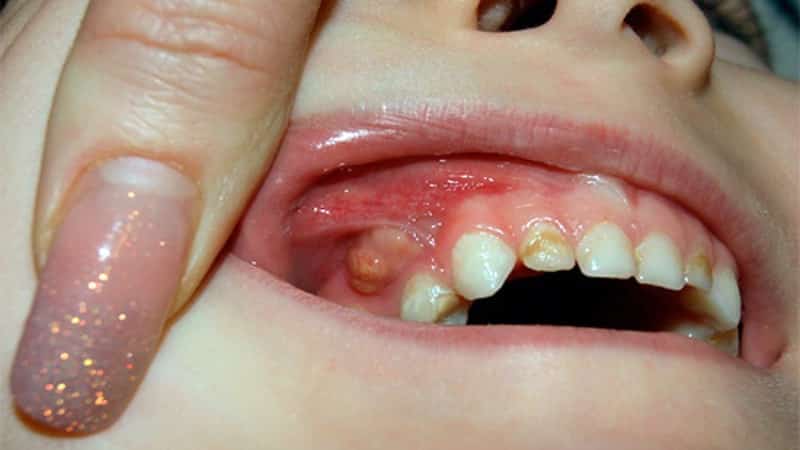

Кроме того, у вашего малыша могут быть и другие причины, вызывающие беспокойство. Обратите внимание на фотографии опухших десен у детей.

Часто у малышей диагностируют флюс, который приводит к отечности или образованию свища над воспаленным участком. Это происходит из-за запущенного кариеса. Если дело доходит до периодонтита, коренной зуб может серьезно пострадать. Поэтому важно своевременно лечить все заболевания полости рта.